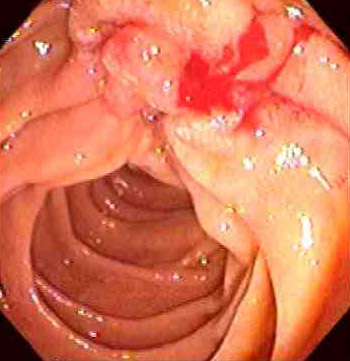

| This adenocarcinoma arose in the ampulla of Vater. Primary small intestinal carcinomas are very rare, but the majority of those that do occur arise in the region of the ampulla, where they may become symptomatic through biliary or pancreatic duct obstruction. The appearance of such a mass on esophagogastroduodenoscopy is seen below, and following placement of a stent for drainage. |